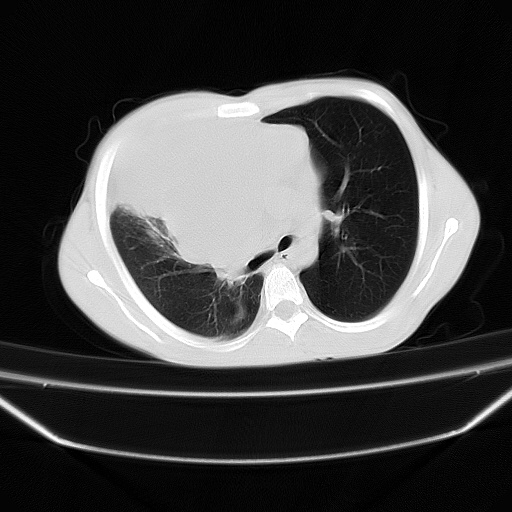

以下是引用zjzjr在2008-7-20 12:57:00的发言:[br]考虑为生殖源性肿瘤(内胚窦瘤),侵袭性胸腺瘤可能性大;右侧少量胸腔积液。

以下是引用xinliheng001在2008-7-20 21:17:00的发言:[br]右纵隔巨大分叶状软组织均质密度肿块,右上肺叶受压明显,纵隔右移、胸膜受累有少量积液和结节样增厚。应增强扫描一定会有更具诊断价值的信息。

以下是引用xinliheng001在2008-7-20 21:17:00的发言:[br]右纵隔巨大分叶状软组织均质密度肿块,右上肺叶受压明显,纵隔右移、胸膜受累有少量积液和结节样增厚。应增强扫描一定会有更具诊断价值的信息。